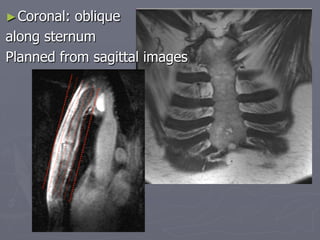

►Coronal: oblique

along sternum

Planned from sagittal images